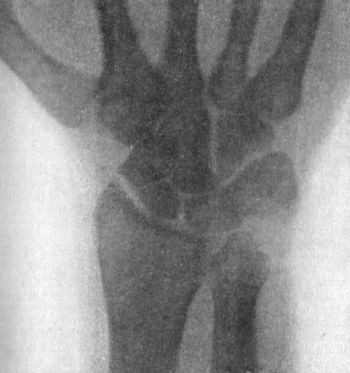

109 49.Radiogram showing Fracture of Navicular (Scaphoid) Bone

111 50.Dorsal Dislocation of Wrist at Radio-carpal Articulation